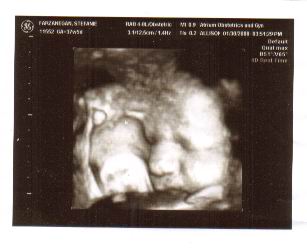

An early view of Max

I became pregnant in May, realizing it only two weeks after we got our puppy, Baron. Well, what's another baby? We are all eagerly anticipating the arrival of Max, whom you see pictured here, in a 4D photograph the technician took of him. He is very snugly contained within my belly--his appearance is a bit compressed, but we're certain that he will stretch out once he makes his appearance. His due date is Valentine's Day, but Frederick is hoping for the 19th, as that was the birthday of the great man for whom he is named, my Father, Max Gray Rogers. I know you always said to not name a child for you, Dad, but I hope you forgive me this once....